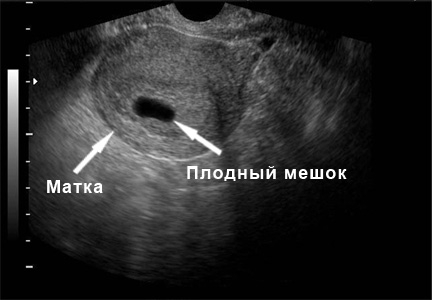

При проведении ультразвукового исследования можно заметить, что форма матки изменилась с грушевидной на более округлую. Эндометрий становится более рыхлым и отечным, а плодный мешок на изображении выглядит как темный овал с четкими контурами, длиной от 5 до 8 см. На этом этапе эмбрион еще не виден. На пятой неделе начинается формирование первичного маточно-плацентарного кровообращения. Ознакомьтесь с календарем УЗИ по неделям беременности с фотографиями, и вы увидите, как постепенно начинается новая жизнь.